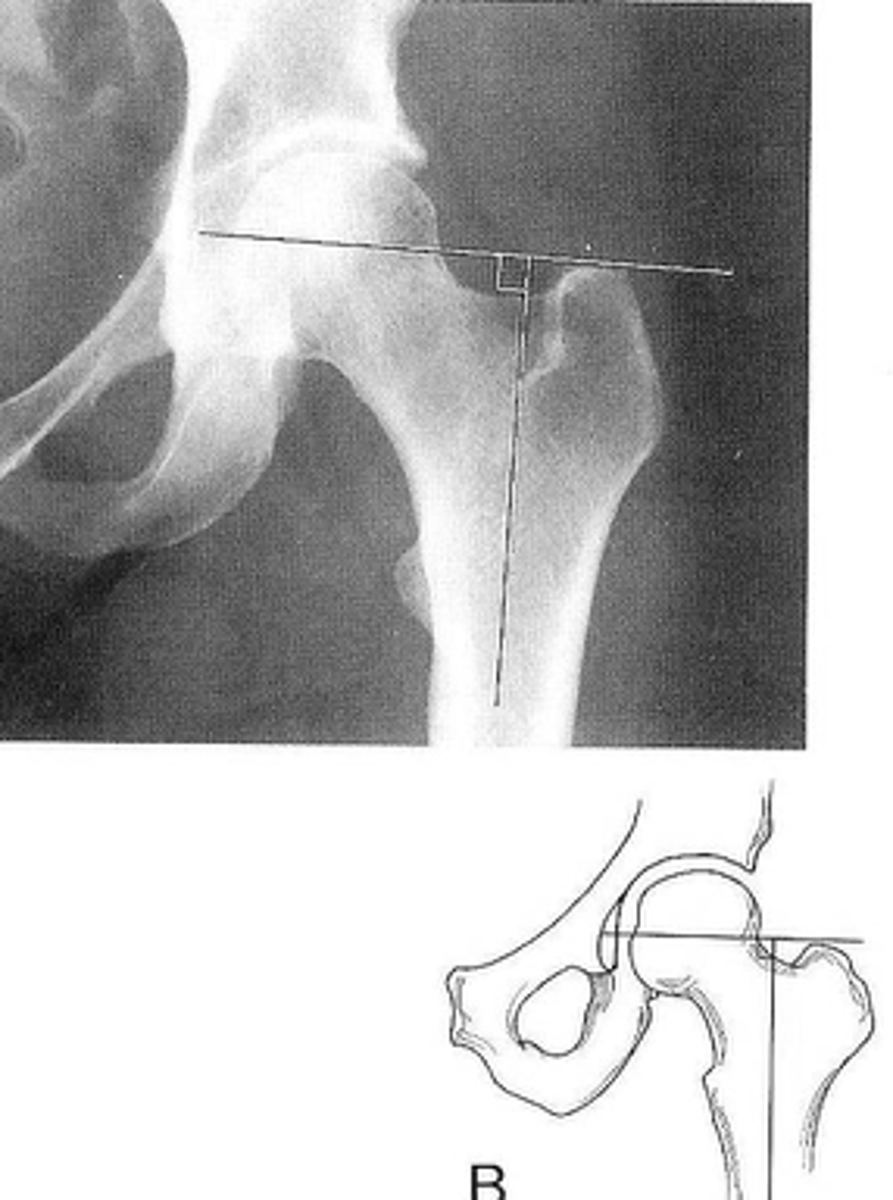

Femoral angle

ID measurement

<p>ID measurement</p>

64

New cards

- AP pelvis

- AP hip

What views are used to measure the femoral angle?

<p>What views are used to measure the femoral angle?</p>

65

- Mid-axis of femoral shaft

- Mid-axis of femoral neck

- Intervening angle

Femoral angle landmarks

<p>Femoral angle landmarks</p>

66

120-130˚

Normal femoral angle measurement

<p>Normal femoral angle measurement</p>

67

Coxa vara

Femoral angle <120˚

<p>Femoral angle &lt;120˚</p>

68

Coxa valga

Femoral angle >130˚

<p>Femoral angle &gt;130˚</p>

69

Skinner's line

70

What views are used to see Skinner's line?

<p>What views are used to see Skinner's line?</p>

71

- Right angle tangent to tip of greater trochanter

Skinner's line landmarks

<p>Skinner's line landmarks</p>

72

Fovea capitis should lie above or at level of trochanteric line

Skinner's line normal measurement

<p>Skinner's line normal measurement</p>

73

Fracture or other causes of coxa vara

Clinical significance of Skinner's line

<p>Clinical significance of Skinner's line</p>